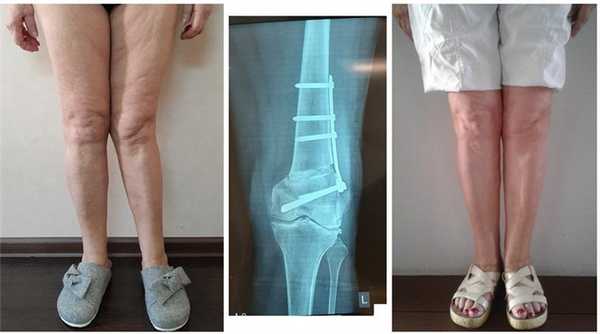

Достаточно грубая варусная деформация у девушки 25 лет исправленная при помощи метода Илизарова. У аппаратной методики есть важное преимущество, она позволяет производить коррекцию в любых плоскостях, одновременное увеличение длины, и одновременно проводить вмешательство на обеих нижних конечностях. Аппарат Илизарова можно спрятать под свободными брюками, и ходить без трости или костылей. Подобная операция не только является профилактикой развития в последующем гонартроза с поражением внутренних отделов коленных суставов, но так же значительно влияет на эстетику нижних конечностей, что крайне важно, когда мы говорим о девушках.